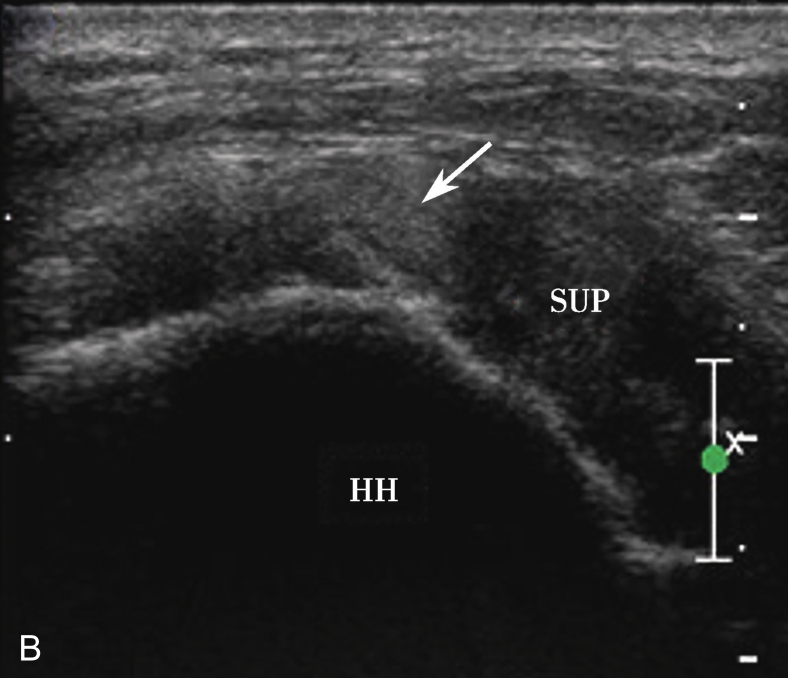

A.超声引导下滑囊内注入超声造影剂后,滑囊呈线状高增强(箭头);B.注入造影剂后的滑囊(箭头),冈上肌腱(SUP)连续性好,未见撕裂,HH:肱骨头

A.超声引导下滑囊内注入超声造影剂后,滑囊呈线状高增强,肌腱内可见局限性高增强,提示肌腱滑囊面部分撕裂(箭头);B.二维超声显示冈上肌腱(SUP)回声不均匀(箭头),但未见明显撕裂,HH:肱骨头